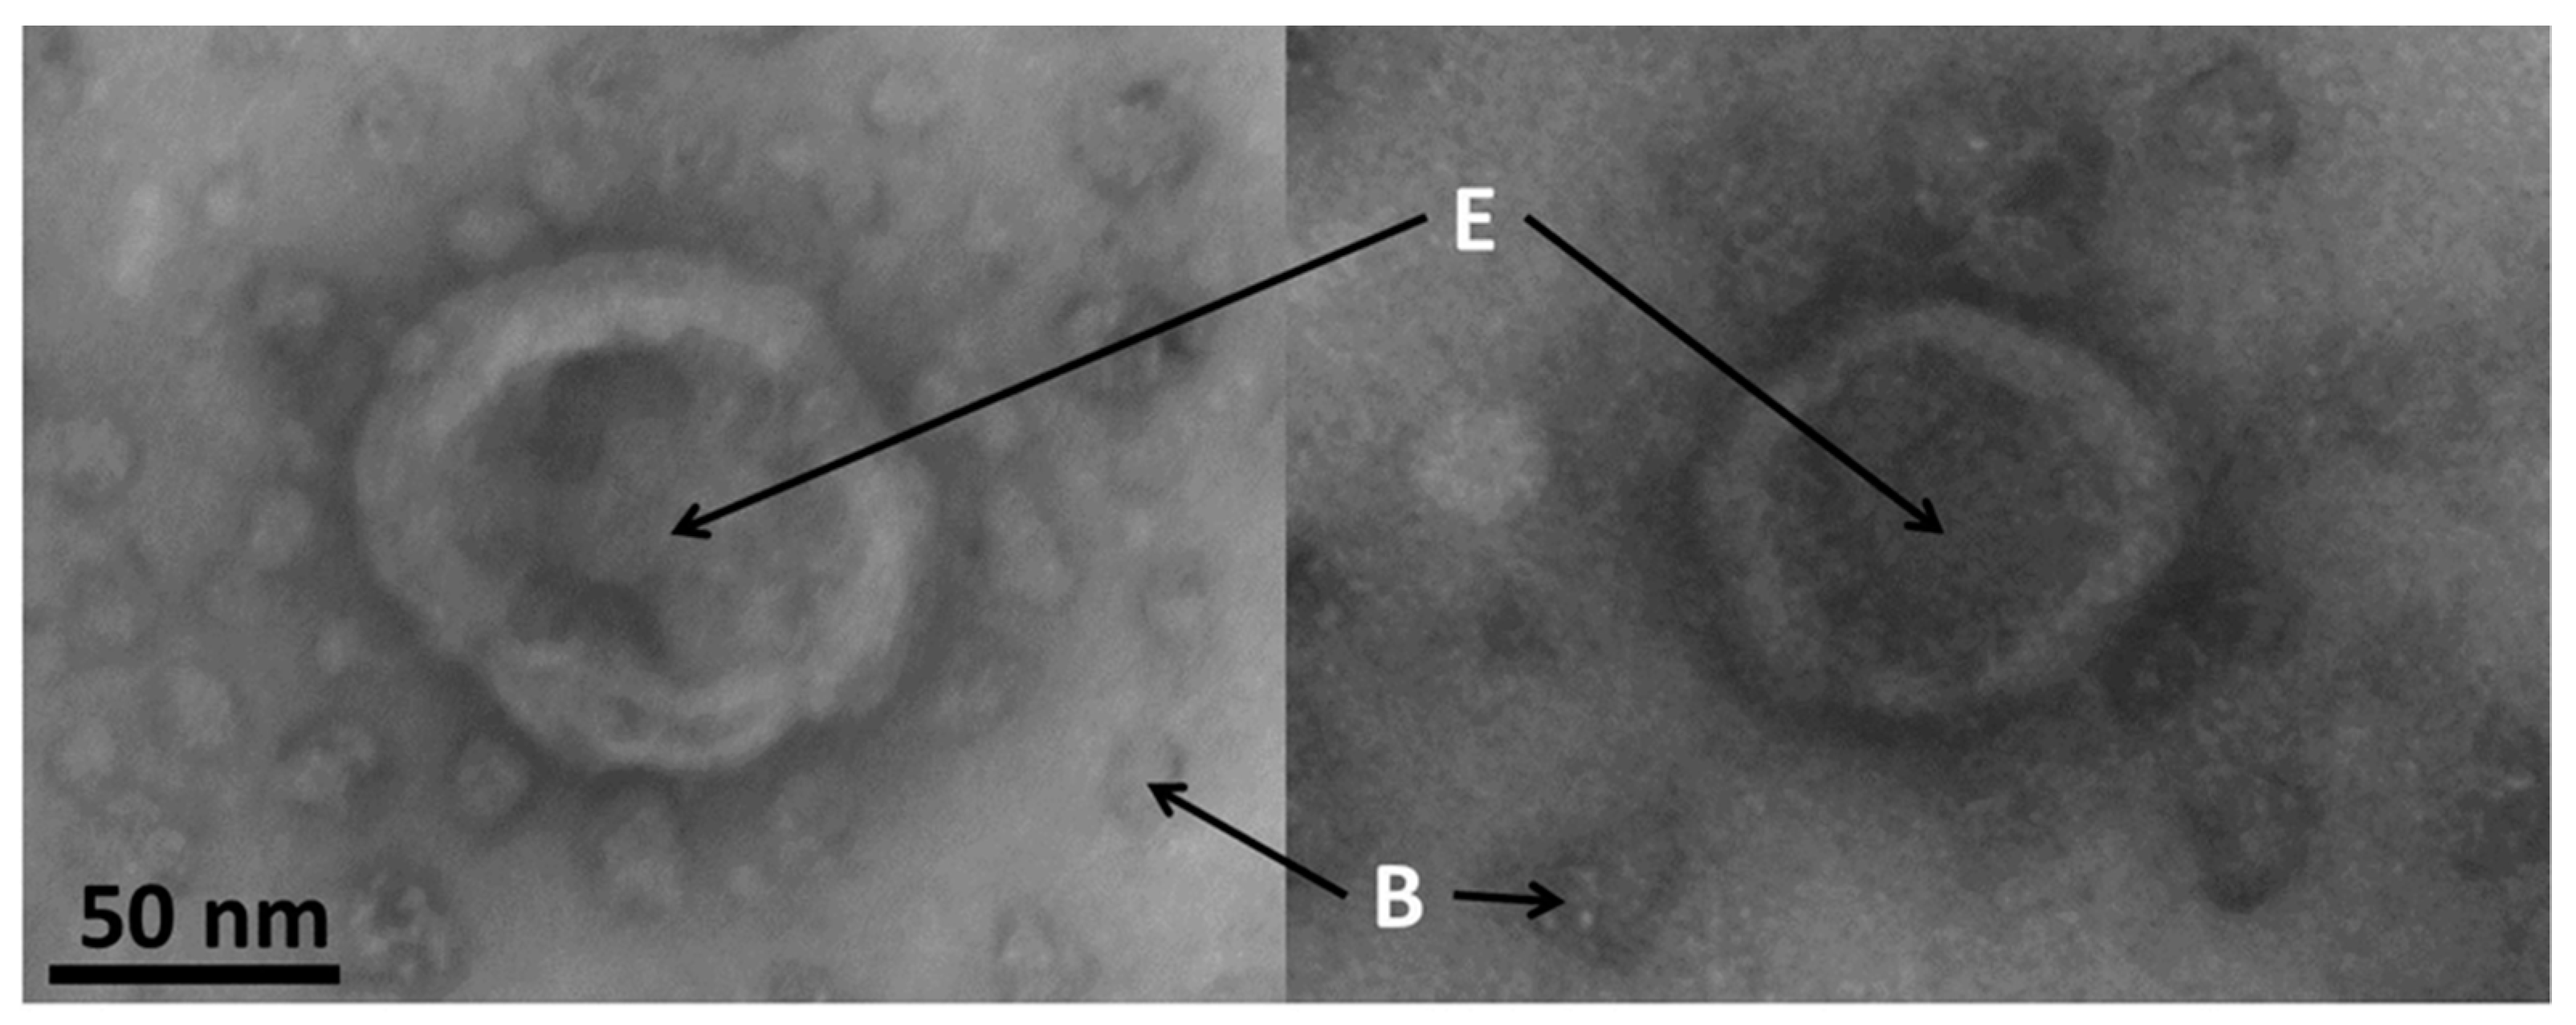

3.7. Electron Microscopy of Exosomes

Typical images of exosomes made by electron microscopy are shown in the Figure 7. The size of the exosomes in this study was confirmed to be around 85 nm.

Exosomes appeared to have a spherical shape with a typical central inflation caused by samples preparation and drying. These morphological data clearly demonstrate the exosomal identity of samples isolated using a combination of flow cytometry and magnetic beads.

Figure 7. Typical images of exosomes made by electron microscopy. E: exosomes; B: magnetic beads. Detailed information on the preparation of the samples is found in Section 2.8. Scale bar = 50 nm.